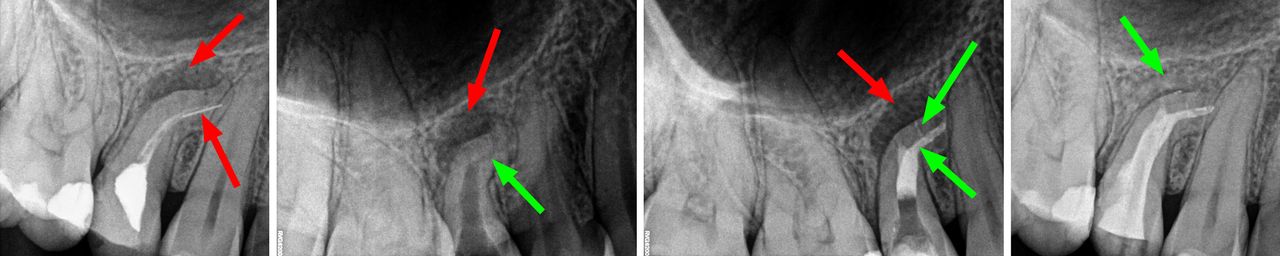

- Usuwanie złamanych narzędzi kanałowych oraz innych ciał obcych pozostawionych w kanałach korzeniowych

- Specjalizujemy się w powtórnym leczeniu kanałowym i leczeniu powikłań co oznacza, że mamy wieloletnie doświadczenie w usuwaniu złamanych instrumentów kanałowych w szybki, bezbolesny i nieinwazyjny sposób. Dr Gończowski jest autorem specjalistycznego zestawu mikroinstrumentów (FRS®) przeznaczonych do usuwania ciał obcych z kanałów korzeniowych